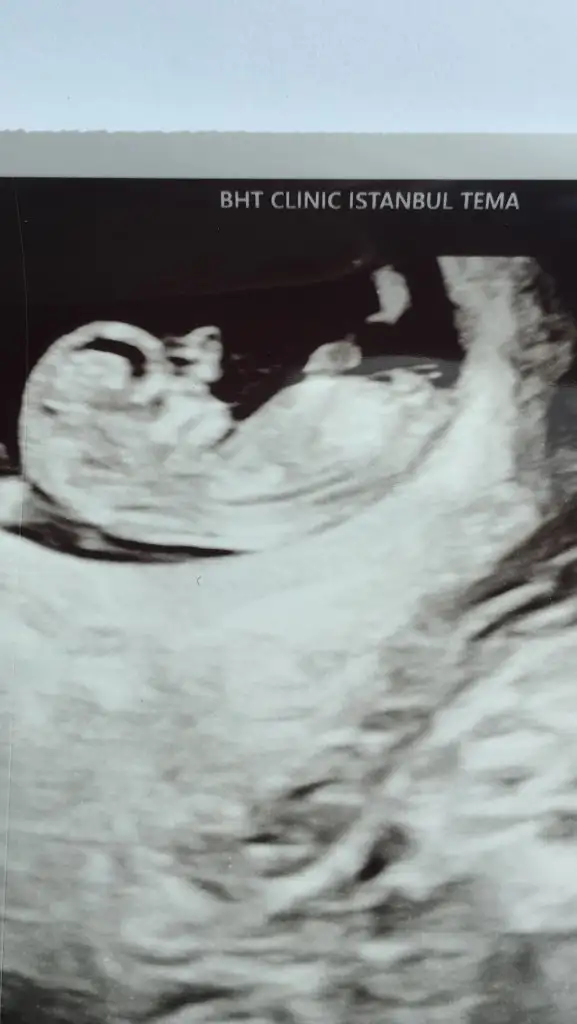

Ikra meyra Ikra meyra 14 hafta 4 günlük. Rica etsem tahminde bulunur musun

ANLAYAN ARKADAŞLAR BANA DA YORUM YAPABLİR Mİ ?:))